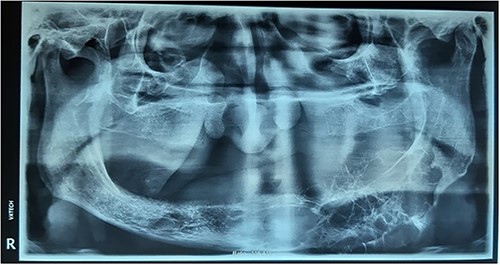

No evidence of recurrence was observed after 2 years (Fig. 8).

Postoperative radiographs. (A) 3D view of the reconstruction plate. (B) Panoramic view of the reconstruction plate after 24 months.